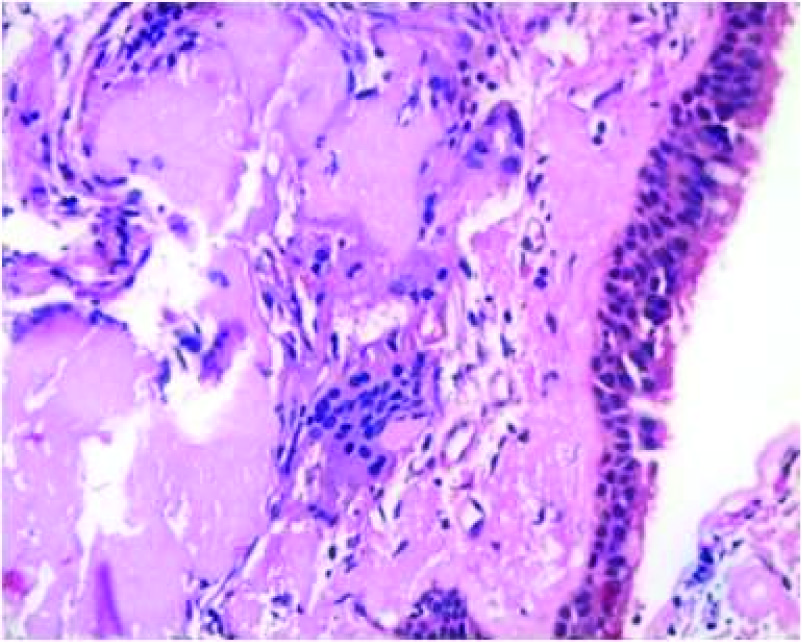

Transbronchial lung biopsy was done and showed subepithelial deposits of acellular eosinophilic homogenous material resembling amyloid [Table/Fig-3]. Some of these deposits formed casts surrounded by inflammatory cells composed of lymphocytes, histiocytes and multinucleate giant cells [Table/Fig-4].These deposits showed apple green birefringent under polarising microscopy using Congo red stain [Table/Fig-5]. Thioflavine T stained the deposits. On immunohistochemistry Lambda light chain antibody intensely stained the deposits [Table/Fig-6]. Kappa light chain antibody was negative.

Subepithelial deposits acellular eosinophilic homogenous material resembling amyloid, H&E 400x magnification